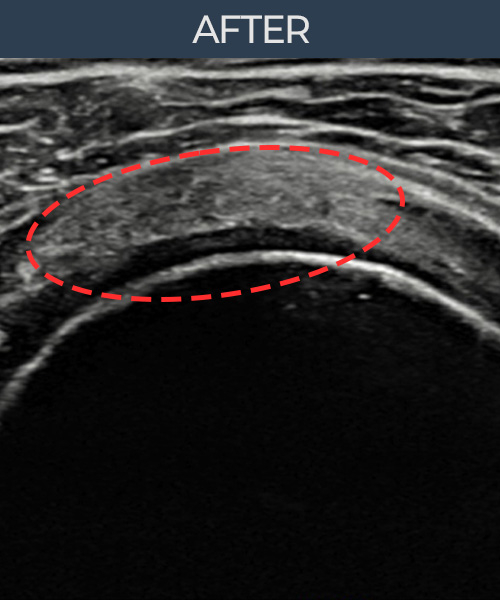

수천건의 수술 경험을 바탕으로 정확히 진단하여

인대파열을 비수술로 치료합니다.

플래티넘정형외과에서는 수술이 필요없는 인대파열만을

정확히 진단하여 특허받은 술기로 비수술로 치료합니다.